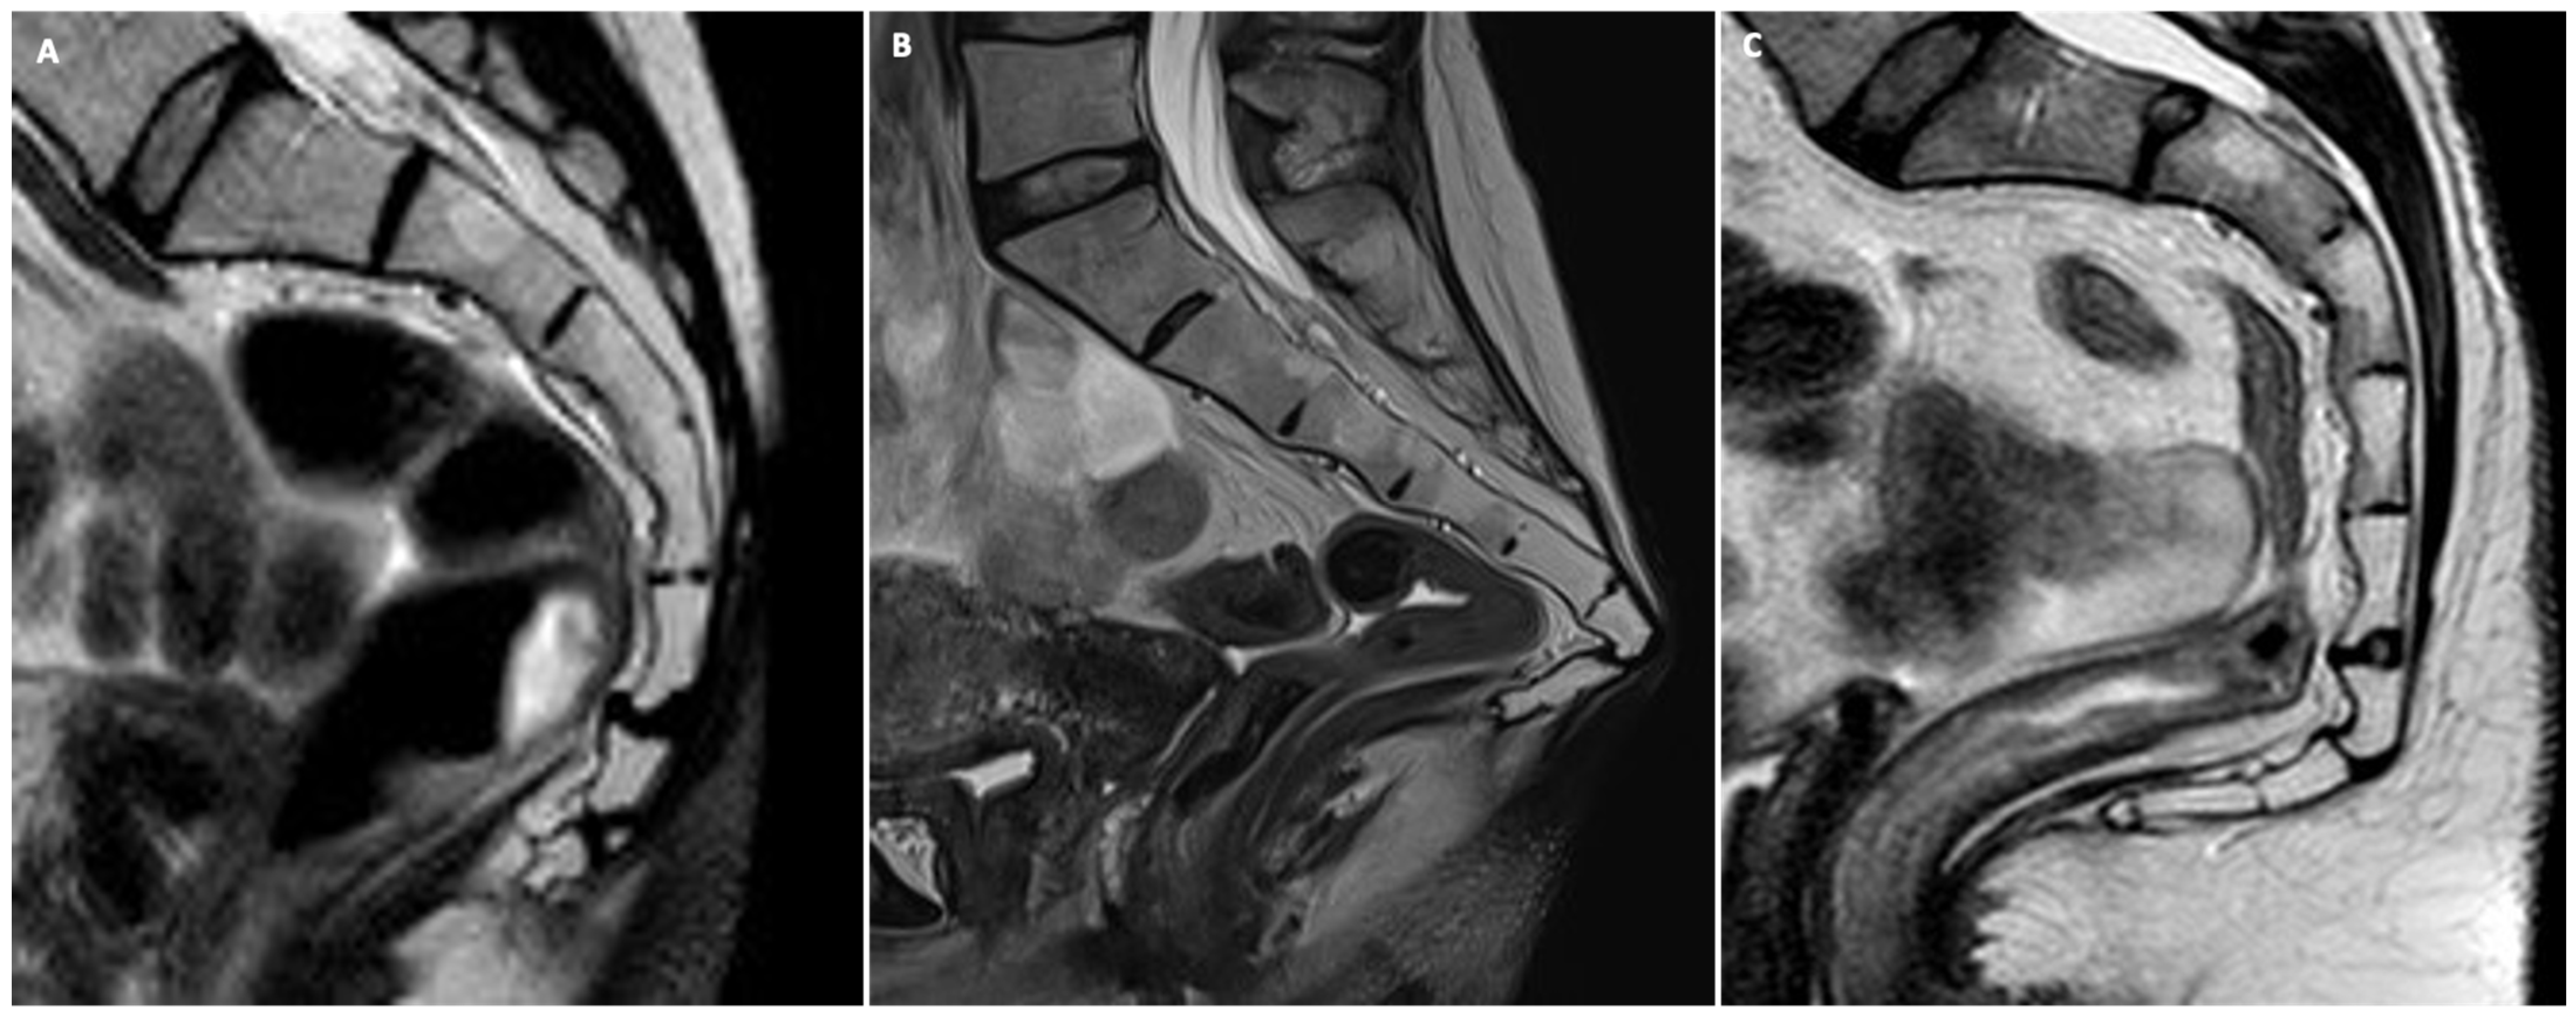

- Anal sphincter complex: This shows variable composition and signal intensity on axial T2-weighted images depending on the level. The upper part consists of the internal sphincter, longitudinal muscle, and puborectal muscle. The middle part features the intersphincteric space, which appears as a high-signal-intensity, slit-like space between the internal sphincter (5 mm thick, intermediate signal intensity) and the external sphincter (1.5 mm thick, low signal intensity). A thin hypointense circular structure within this space represents the longitudinal muscle, which is a continuation of the outer longitudinal smooth muscle of the rectum. The lower part contains the external sphincter and the longitudinal muscle layer. On mid-coronal T2-weighted images, the thicker inner layer is formed by the two halves of the internal sphincter in apposition, while the intersphincteric space is visible as a thin, high-signal-intensity layer. At the outer margin, a cleft divides the puborectalis muscle (above) from the external sphincter (below). On midsagittal T2-weighted MR images, the anal sphincter appears as a low-signal-intensity, homogeneous, cylindrical structure, approximately 4 cm long, composed of muscle layers extending from the attachment of the levator ani muscle to the rectum. Lastly, the perianal spaces are clearly seen as two symmetrical, high-signal-intensity, fat-containing, pyramid-shaped spaces surrounding the hypointense anal canal, with multiple fibrous septa. The apex is visible at the origin of the V-shaped levator ani muscle, along with the supralevator space above it.

- Dyssynergia: defined as transient or persistent paradoxical contraction of either the puborectalis muscle or the anal sphincters during evacuation. This is seen as a persistent impression at the posterior margin of the anorectal junction, along with a lack of anorectal angle (ARA) widening and a failure of anal canal widening.